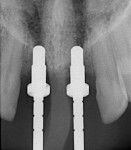

The CT scanner's imaging allows us to create custom made surgical guides specific to each patient.  These surgical guides allow the precise placement of dental implants for optimal functional and esthetic results.

CT Guided Custom Implant Placment